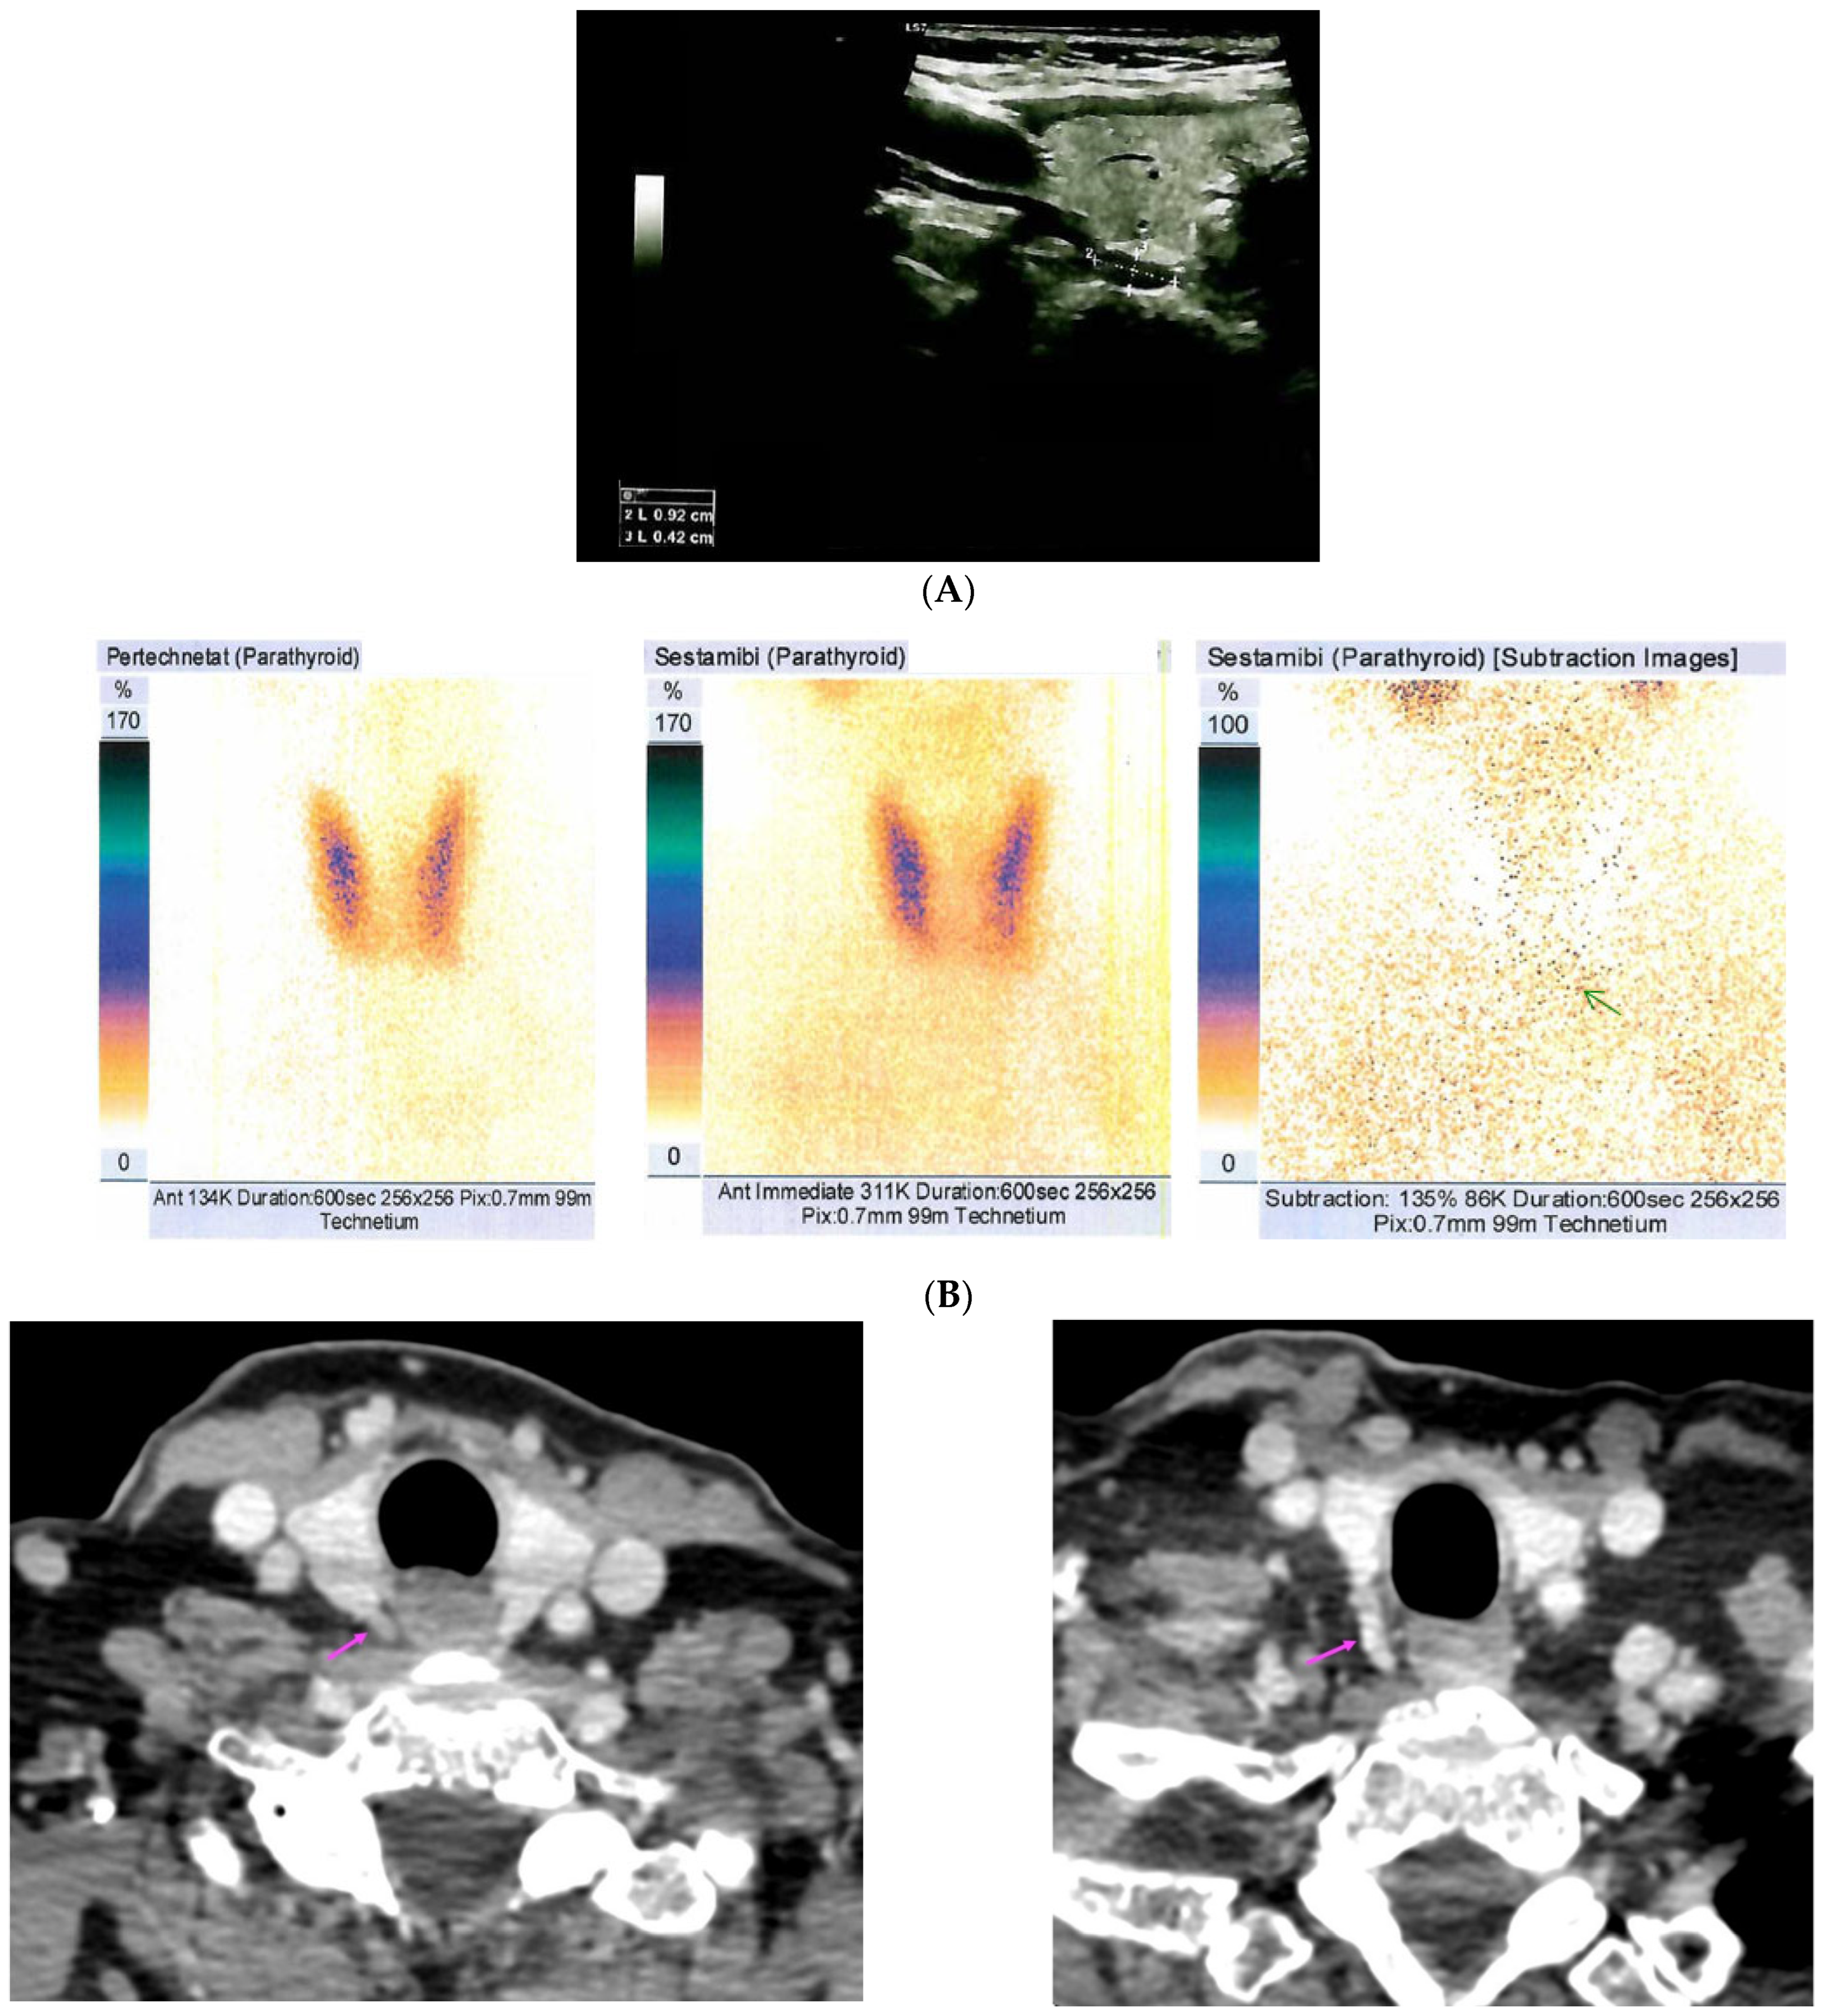

| [37] | US: six nodules of 5 mm to 16 mm located subcutaneously anterior of right sternocleidomastoid muscle 99m-Tc sestamibi scintigraphy: no hyper-functional foci CT: similar to US | Parathyromatosis |

| [38] | 99m-Tc-MIBI imaging (SPECT/CT): three foci of elevated uptake on early phase with slow washout on delayed phase | Hyperplastic parathyroid tissues |